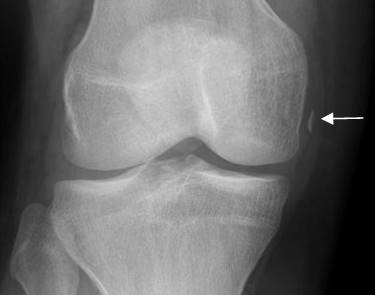

Fig 205. Fractura de Segond.

A: Rx AP de rodilla. Fragmento óseo por encima de la cabeza del peroné, paralelo al borde del platillo tibial, que corresponde a fractura de Segond.

B: RM coronal en STIR. Contusión asociada del cóndilo femoral y platillo tibial lateral.

C: RM sagital en STIR. Este tipo de lesión se asocia con ruptura del LCA.